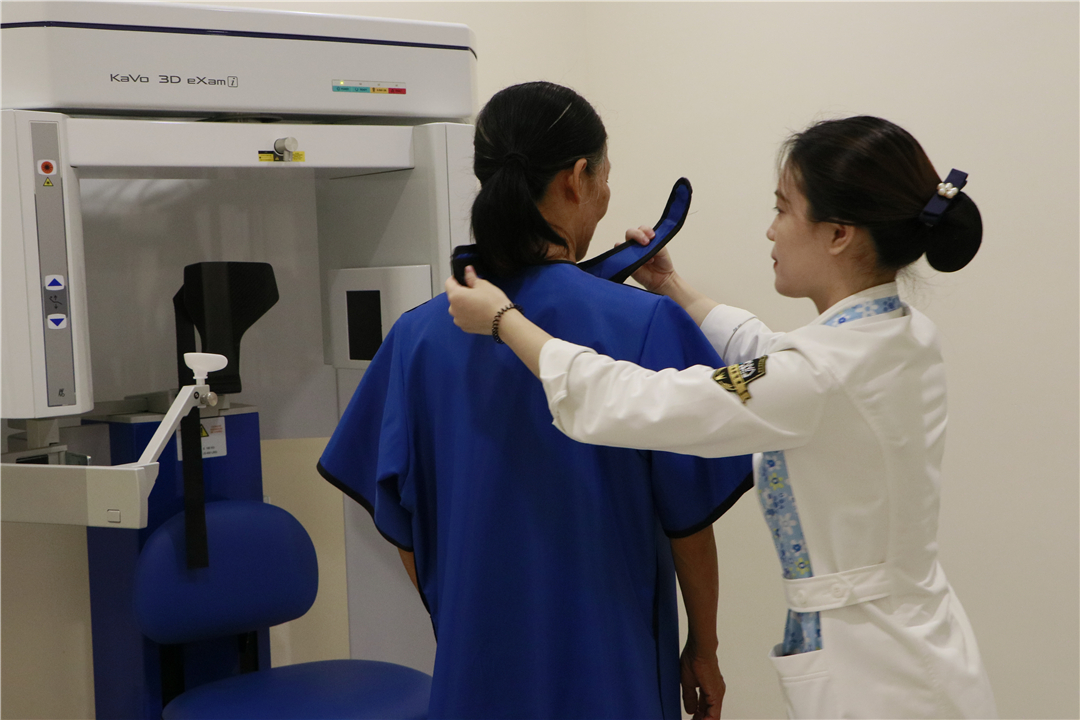

签到、拍片、引导叔叔阿姨们到会场休息等候,活动有条不紊的进行。很多人对拍摄CT存在疑虑,担心辐射影响等等。

而且,口腔CT的辐射量,远低于每个人每年可接受的辐射量国际标准。不仅如此,拍摄CT前,影像科工作人员都会要求并帮助患者穿上防辐射的铅衣铅裙,做好安全防护。